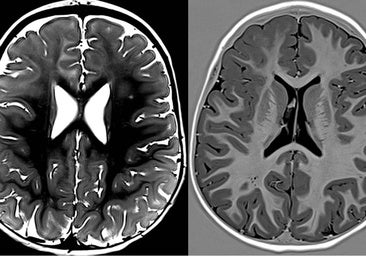

Los especialistas aseguran que ya hay datos clínicos que apuntan a que, aplicado en combinación con inmunoterapia, estas corrientes específicas pueden aumentar la supervivencia en pacientes con diferentes tumores sólidos. Y es que los TTFields han demostrado eficacia, en primer lugar, en los tumores cerebrales, «en concreto, en uno muy agresivo en el cerebro llamado glioblastoma multiforme», subraya el Dr. Calles.

Según la Dra. Vaz, tras un estudio de fase III, donde se vio que mejoraba la supervivencia en estos tumores agresivos, la actividad de los TTFields ha quedado demostrada, por lo que están aprobados en la actualidad. El tratamiento se aplica tras la cirugía y sumado al tratamiento habitual de radioterapia y quimioterapia. «También se ha observado que es un tratamiento bien tolerado y con pocos efectos secundarios», apunta la especialista.